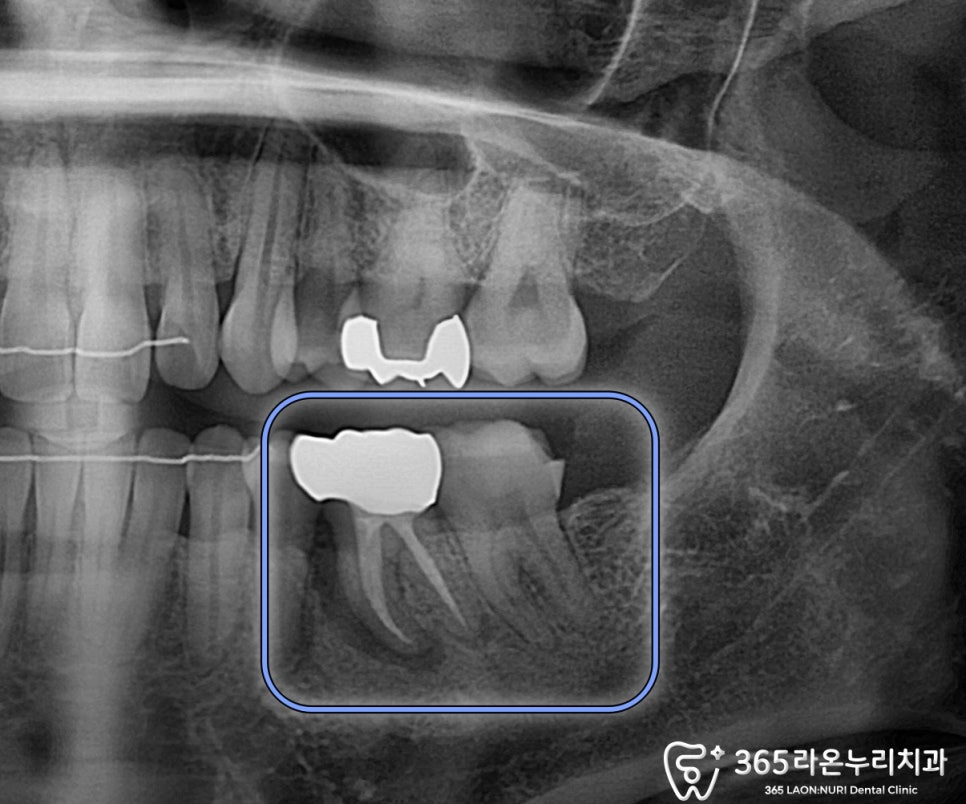

먼저 문제가 있던 어금니를

보면 엑스레이에서는

뿌리 쪽 염증이 보이지만,

구내 사진에서는 큰 문제가 안 보입니다.

오산대역 치과 에서

CT를 찍어 치조골 두께 및 염증을

확실하게 파악했습니다.

전반적으로 골소실이 매우 심하고

뼈도 많이 녹아있습니다.